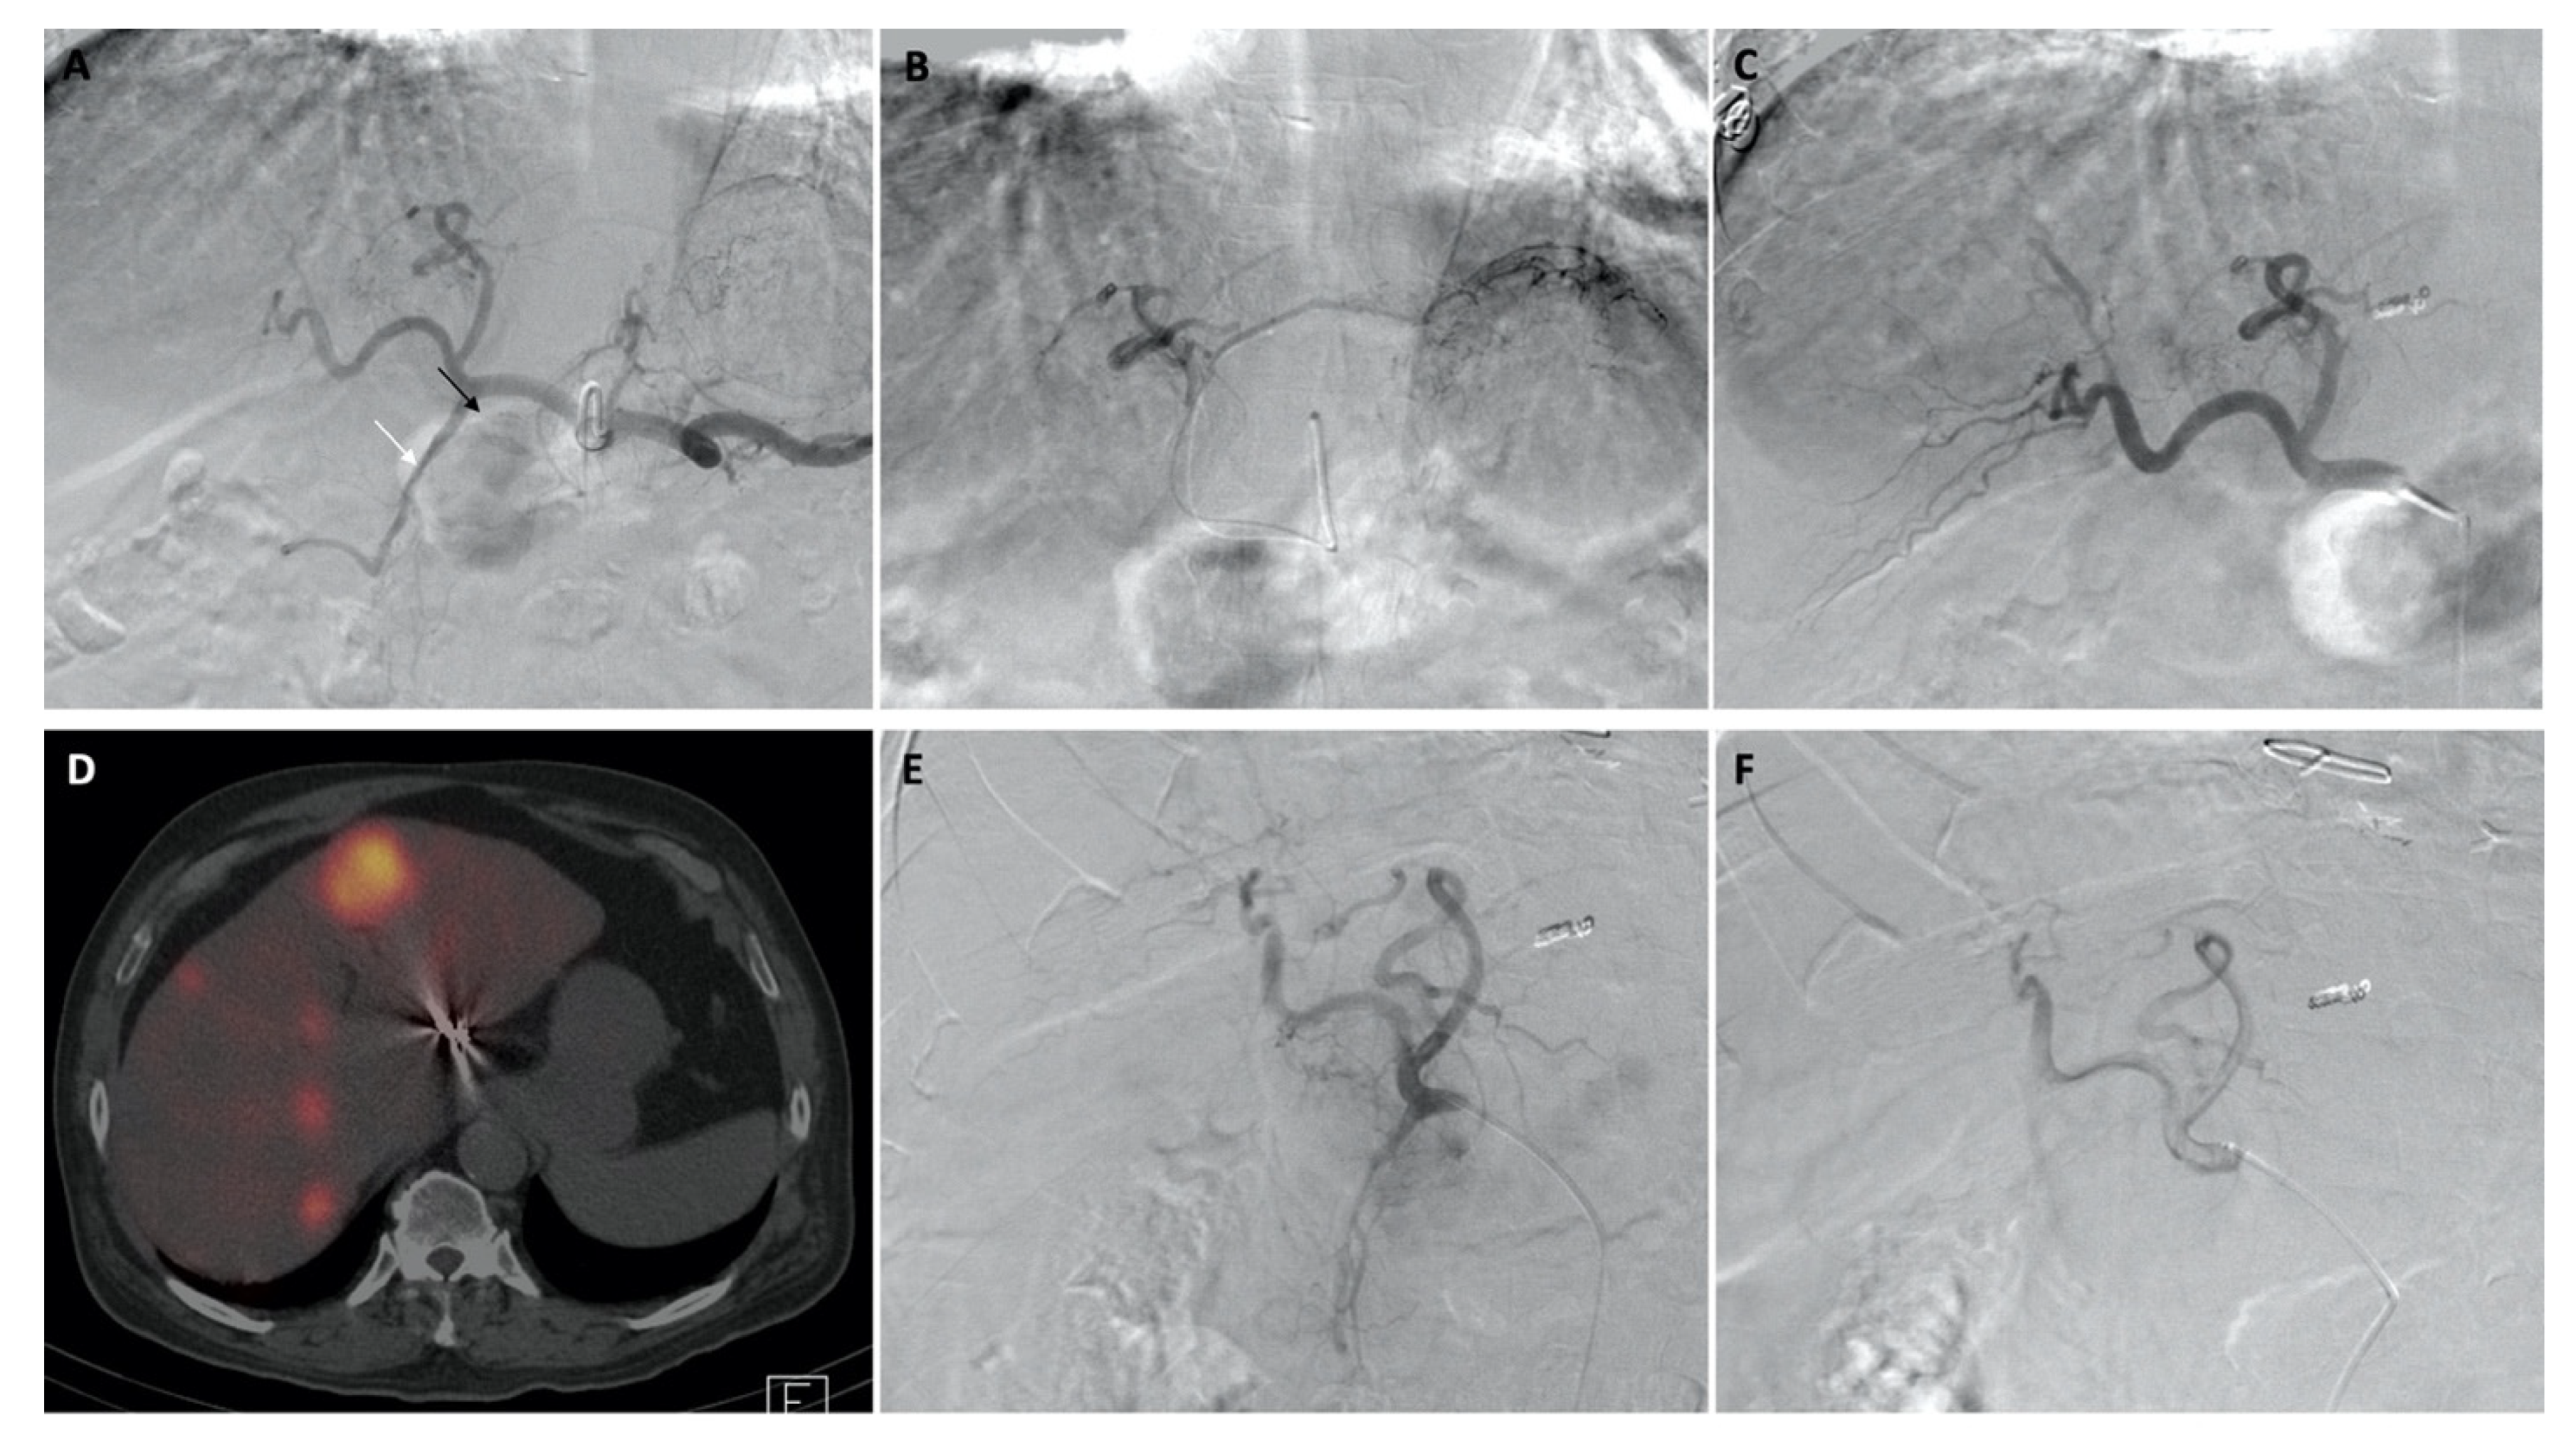

Temporary Reversal of Hepatoenteric Collaterals during 90Y Radioembolization Planning and Administration

Habibollahi, P.; Odisio, B.C.; Gurusamy, V.; Kuban, J.D.; Avritscher, R.; Abdelsalam, M.E.; Chasen, B.A.; Murthy, R.; Mahvash, A. Temporary Reversal of Hepatoenteric Collaterals during 90Y Radioembolization Planning and Administration. Curr. Oncol. 2022, 29, 9582-9592. https://doi.org/10.3390/curroncol29120753